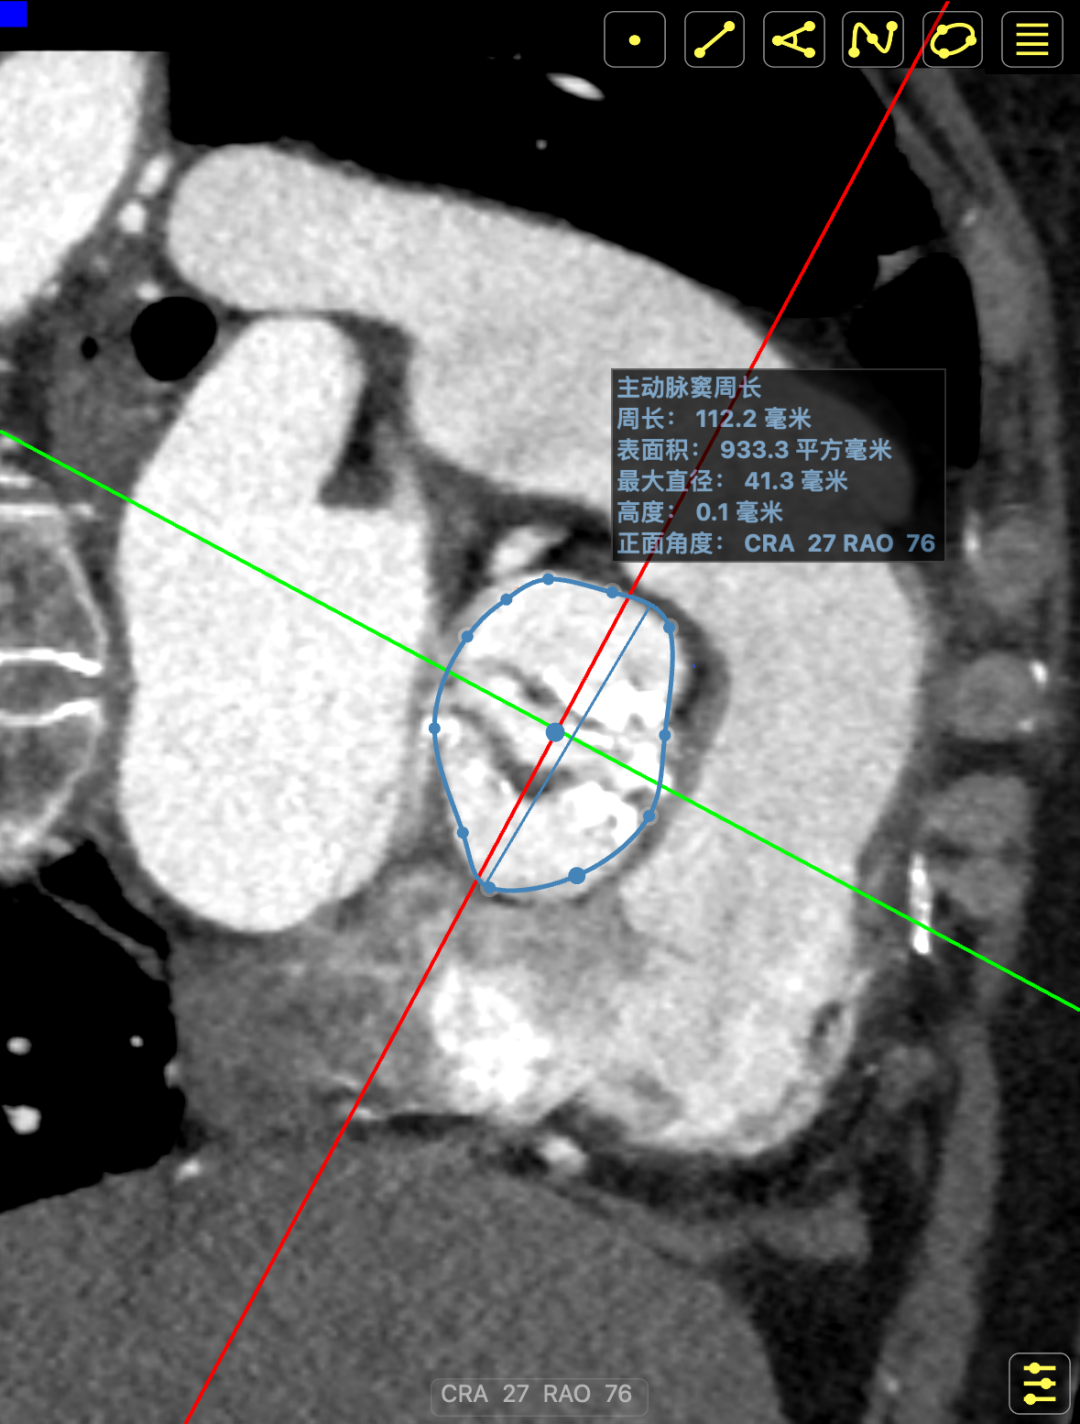

术前CT提示

主动脉瓣多发钙化,主动脉瓣为type0型二叶瓣中重度钙化。主动脉瓣环面积折算直径约24mm。患者双侧冠脉开口高度可(左冠14.46mm,右冠18.29mm),主动脉升弓降部管壁不规则并钙化斑块影,主动脉弓并龛影。升主动脉管径36mm,降主动脉管径22mm。腹主动脉、双侧髂动脉管壁不规则并可见钙化斑块影,双侧髂总动脉及其分支髂内动脉管腔轻度狭窄。

CT影像